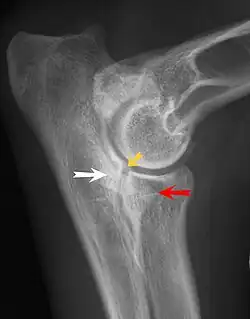

Most primary lesions are related to osteochondrosis, a disease of the joint cartilage, and osteochondritis dissecans (OCD), the separation of a flap of cartilage on the joint surface. Other common causes of elbow dysplasia include an ununited anconeal process (UAP) and fragmented or ununited medial coronoid process (FCP or FMCP).[1]

The most common cause is osteochondrosis, which is a disease of the joint cartilage, and osteochondritis dissecans (OCD or OD), the separation of a flap of cartilage from the joint surface[1] as a result of avascular necrosis, which in turn arises from failed blood flow in the subchondral bone.[3]

In OCD, the normal change of cartilage to bone in the development of the joint fails or is delayed. The cartilage continues to grow and may split or become necrotic. The cause is uncertain, but possibly includes genetics, trauma, and nutrition (including excessive calcium and decreased vitamin C intake).[4] OCD lesions found in the elbow at the medial epicondyle of the humerus are caused by disturbed endochondral fusion of the epiphysis of the medial epicondyle with the distal end of the humerus, which may in turn be caused by avulsion of the epiphysis.[5] Specific conditions related to OCD include fragmentation of the medial coronoid process of the ulna (FMCP) and an ununited anconeal process of the ulna (UAP). All types of OCD of the elbow are most typically found in large breed dogs, with symptoms starting between the ages of 4 and 8 months.[4] Males are affected twice as often as females. The disease often affects both elbows (30 to 70 percent of the time), and symptoms include intermittent lameness, joint swelling, and external rotation and abduction of the paw.[6] Osteoarthritis will develop later in most cases.

UAP is caused by a separation from the ulna of the ossification center of the anconeal process.[7] FMCP is caused by a failure of the coronoid process to unite with the ulna.